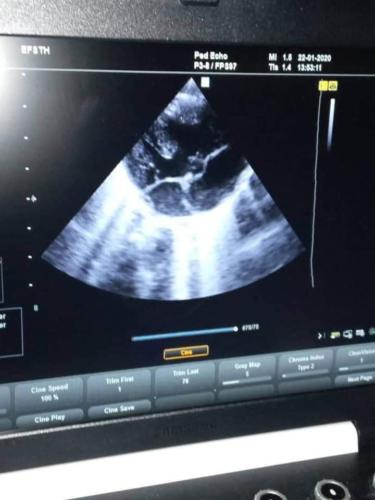

Por primera vez, en el Edward Francis Small Teaching Hospital, de la capital de Gambia, se pueden diagnosticar cardiopatías congénitas gracias a los avances en el departamento de Ecocardiografía, y por la presencia en esta tierra hermana, también por vez primera, de un especialista cubano en cardiología .

Para ejemplificar, presentamos el caso de un recién nacido que desde su nacimiento presentó un cuadro de cianosis generalizada, sobre todo a la manipulación y al llanto.

Fue valorado por el cardiólogo y se le diagnosticó una Tetralogía de Fallot. Se orienta tratamiento adecuado gracias al trabajo conjunto del equipo de médicos cubanos integrado por: la Neonatóloga Dra. Celina Drialis Llacer De la Cruz, el Cardiólogo Dr. Roger García Kindelan y la Lic. Rosa María Núñez.